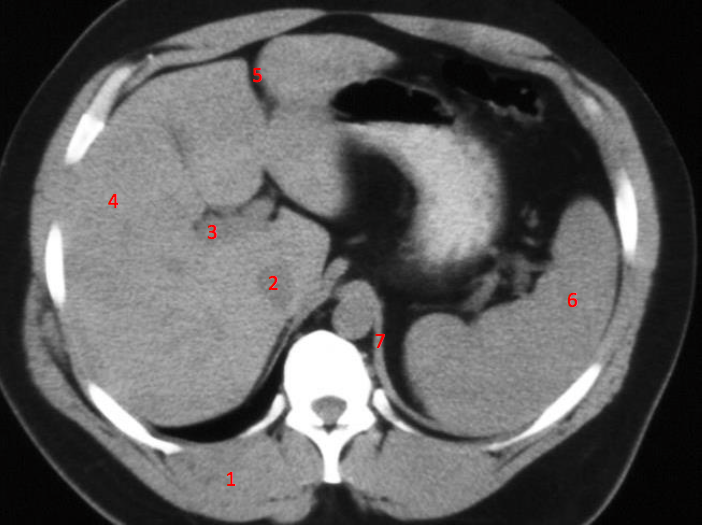

4

Number 2?

IVC

16

17

Number 4?

18

Number 1?

19

20

Number 6?

Portal vein

Number 5?

Falciform/round ligament